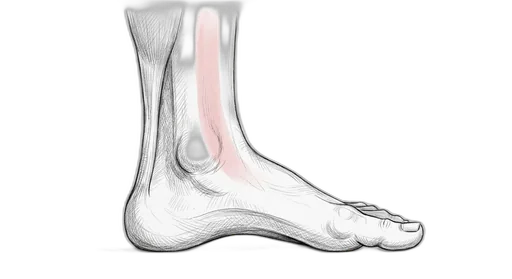

Achilles & Calf